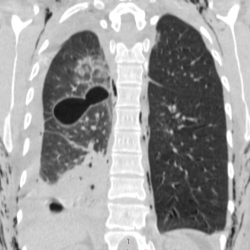

Добрый день. Подскажите пожалуйтса как описать в нижних отделах левого легкого.. как образование слева ?